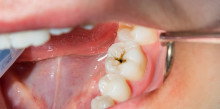

Der vorliegende Fallbericht schildert den Versuch des Zahnerhalts bei einer Kronen-Wurzel-Fraktur mittels intraalveolärer Transplantation und anschließender...

Der vorliegende Fallbericht schildert den Versuch des Zahnerhalts bei einer Kronen-Wurzel-Fraktur...